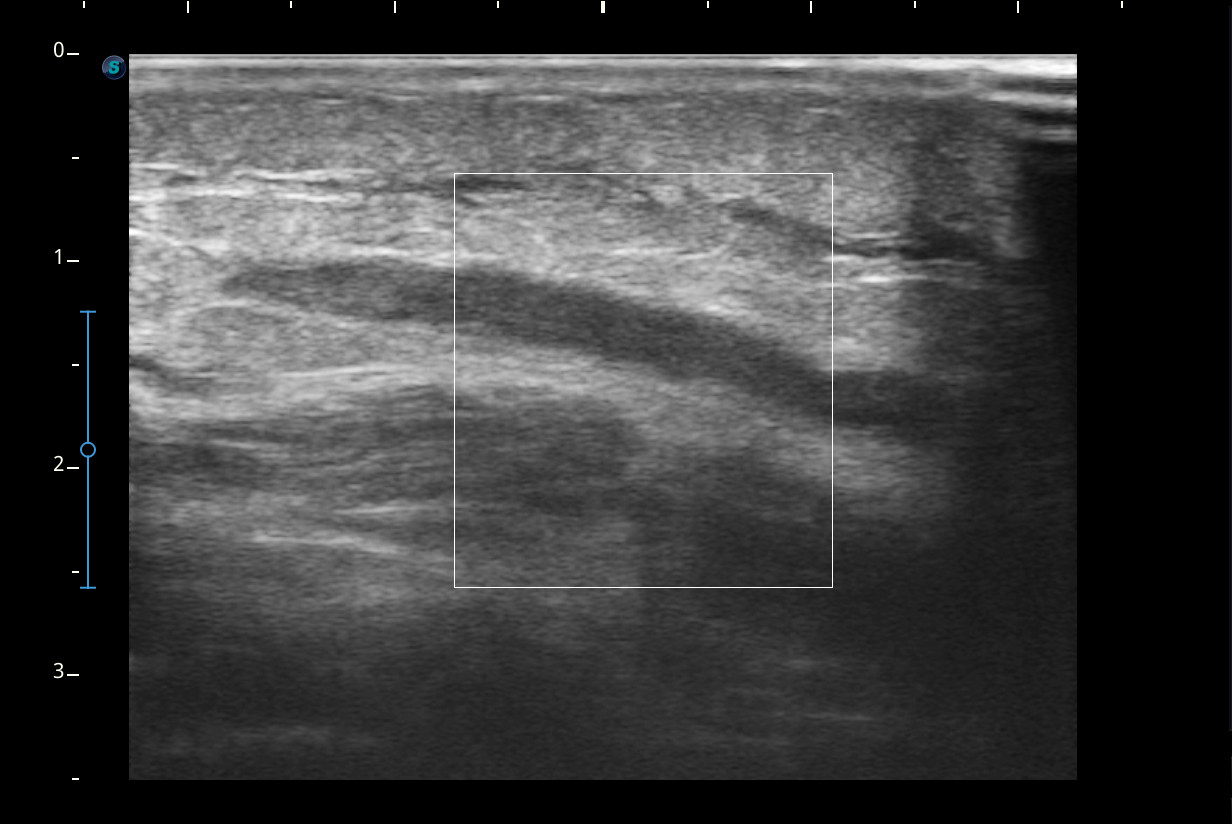

Se visualiza congestión del tejido subcutáneo del brazo y ocupación de la luz de la vena basílica del brazo por un trombo.

Se remitió a urgencias pero le realizan solamente radiografía del brazo y acude de nuevo a consulta. Nos ponemos en contacto con el SUH y realizan ecografía Doppler.